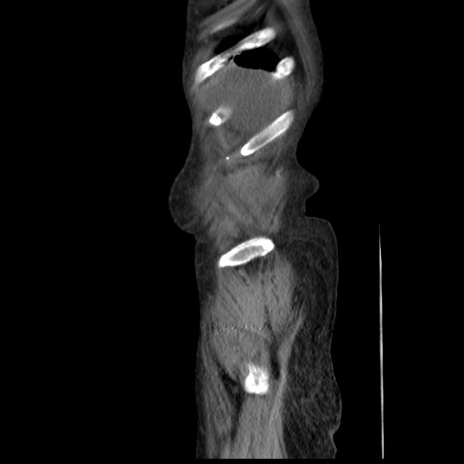

症例31(矢状断像)

【症例】80歳代 女性

【主訴】腹部膨満感

【現病歴】他院にて肝硬変にてフォロー中。1週間前から便秘、腹部膨満感、臍部腫瘤あり受診となる。

【既往歴】肝硬変

【身体所見】腹部膨隆あり、皮膚変化なし、疼痛なし。

【データ】WBC 4600、CRP 0.25